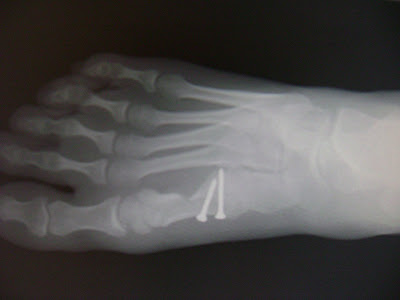

Here is the xray of my foot. as you can see the wonderful pins that will be in my foot for the rest of my life and will make me beep when i go through the air port. but my bones look straight. isn't it wonderful!